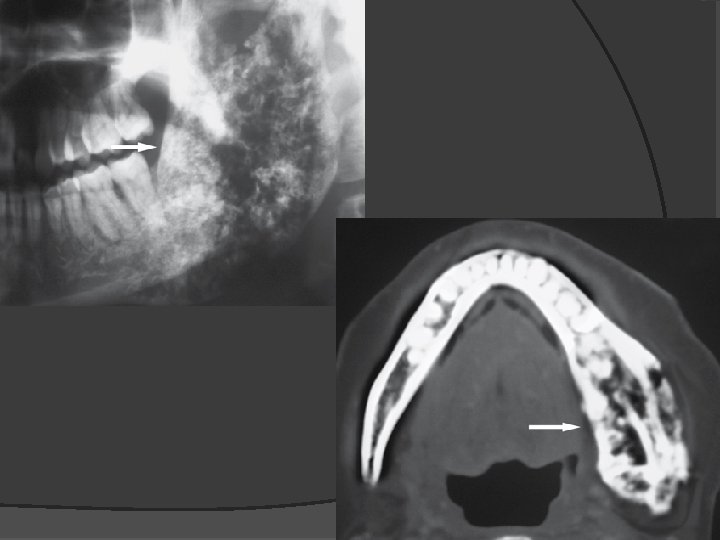

Panoramic view Coronal CT image Axial CT image Coronal T 1 -weighted post-Gd MRI